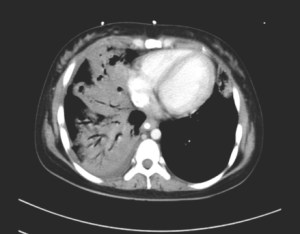

Within a day, she required inotropic support to maintain her blood pressure within physiological limits, and she required mechanical ventilation to support her breathing. A CT thorax showed extensive consolidation and cavitation within both lungs, worse on the right side.